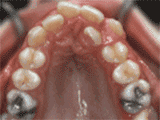

牙齒不齊的原因是先天性還是后天性呢?牙齒不整齊不僅影響美觀,還會影響牙齒健康,例如容易出現(xiàn)牙結石、蛀牙等現(xiàn)象,那么牙齒不整齊的原因是先天性還是后天性呢?我們一起來看看漳州衛(wèi)生職業(yè)學院附屬口腔醫(yī)院醫(yī)生的介紹吧!

牙齒不齊除了先天因素,剩下大部分都是后天造成的,比如長期用嘴呼吸,小時候有咬鉛筆、啃手指的習慣,還有就是乳牙早失、過早失牙等。

不良習慣:比如咬手指,咬上唇或咬下唇習慣,伸舌或吐舌習慣。

牙早失:會出現(xiàn)間隙不足,產(chǎn)生擁擠錯位。

多生牙:多生牙能引起牙、頜系統(tǒng)的形態(tài)功能紊亂。

乳牙滯留:個別牙逾期不脫落為乳牙滯留,可導致繼替恒牙萌出受阻而呈埋伏,或錯位萌出。

乳尖牙磨耗不足:因為兒童吃的食物過軟,所以有的乳尖牙不如其他牙齒磨耗多,因而高出牙弓頜面,產(chǎn)生早接觸,造成前方或側方移動,形成反頜。